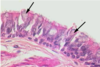

What is this showing in the lungs and why?

Pulmonary TB

Early Mycobacterium tuberculosus - early caseous granuloma , central area of caseous necrosis (CN), surrounded by macrophages (M) which fuse to giant Langerhans cells (L). Arrows = rim of lymphocytes.